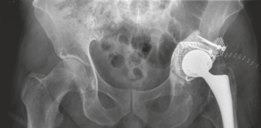

Surgical Decision Making and Classification

The management of massive bone loss in revision THA presents a formidable reconstructive challenge. The primary goals of the intervention are the eradication of particulate debris, the restoration of anatomic hip mechanics (center of rotation, offset, and leg length), the achievement of rigid initial component stability, and the long-term reconstitution of host bone stock.

- Impaction Bone Grafting (IBG) with a Cemented Cup: The technique pioneered by Slooff and the Nijmegen group. This utilizes tightly impacted morselized cancellous allograft to fill cavitary defects and reconstruct segmental deficits (often in conjunction with metallic mesh), followed by the cementation of a polyethylene cup.

We elected to proceed with Acetabular and Femoral Impaction Bone Grafting. The biological rationale for IBG is profound. The tightly packed morselized cancellous allograft provides immediate mechanical stability through the interlocking of the bone chips. Over time, this graft undergoes creeping substitution—a process of simultaneous osteoclastic resorption and osteoblastic bone formation—ultimately incorporating and remodeling into living host bone according to Wolff's Law.